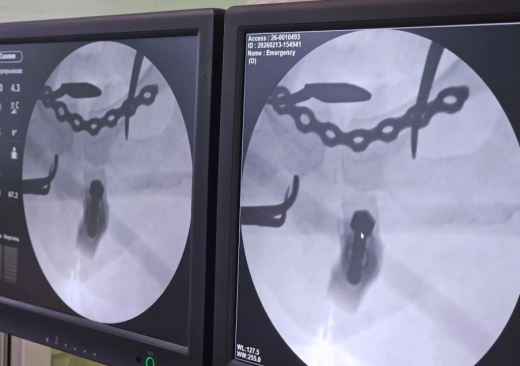

Женщина едва не лишилась жизни из-за неудачной поездки на тюбинге в Воронеже. Как сообщили в региональном Минздраве, от смерти её спасли в БСМП №1. К врачам 41-летняя любительница активного отдыха попала в январе после того, как не удержалась и упала с «ватрушки» на большой скорости. При осмотре выяснилось, что у пациентки перелом боковых масс крестца с двух сторон и разрыв лонного сочленения. – Таз – это основа скелета, и такие повреждения опасны для жизни из-за массивного внутреннего кровотечения с развитием шока, – отметили в Минздраве. – Помощь женщине оказывали, использовав новый аппарат для внешней фиксации переломов. Это оборудование позволяет выполнить стабилизацию максимально быстро и малоинвазивно. Для начала медики восстановили правильное положение костных отломков и зафиксировали их аппаратом. Вся операция заняла всего 20 минут. Спустя некоторое время, когда женщина уже шла на поправку, ей окончательно зафиксировали переломы специализированными металлоконструкциями. – Перелом крестца закрепили канюлированными винтами через проколы, а разрыв лонного сочленения – титановой пластиной через мини-доступ. Сейчас состояние пациентки стабильное, – поделились врачи.